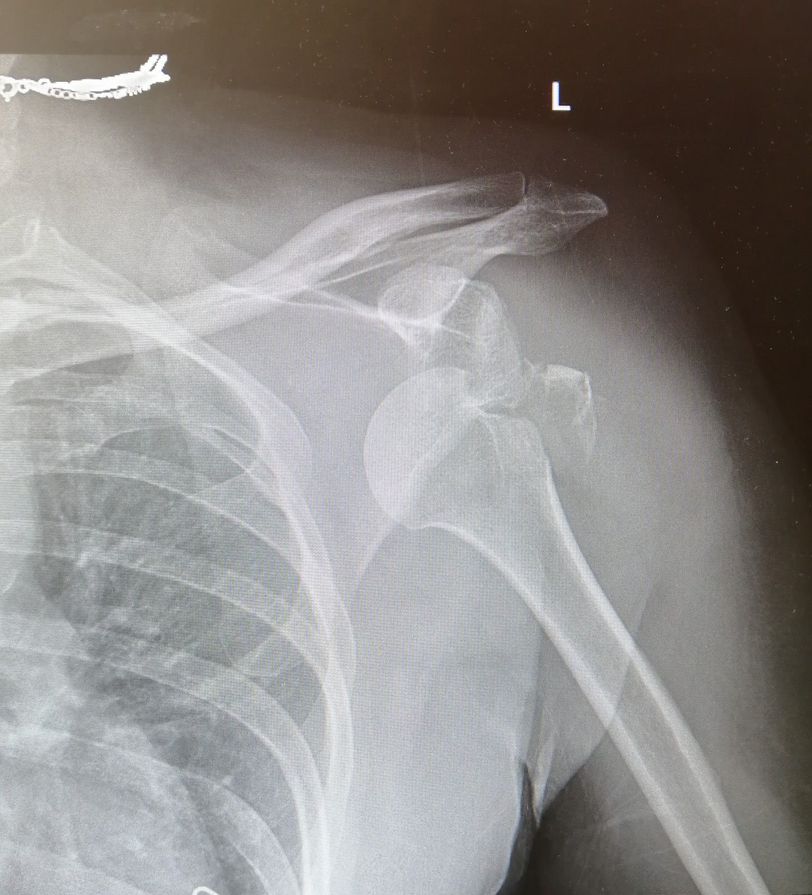

shoulder dislocation with fracture of the greater tuberosity

Left shoulder Ap view